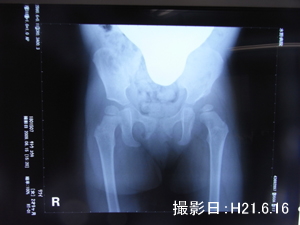

というのも、前回のレントゲン写真を見てもわかるように脱臼してた方の骨と骨には隙間があり

何をしてもかわまないという状態ではないからです(私の判断です)

今回のレントゲンでも変わりなく間が空いています

前回と変わらないだけ良かったと思うけど次回のレントゲンの結果次第では

夜寝る時だけまた装具になる可能性もアリ!という検診結果だったので

これからも注意が必要ですね~

装具をはずしてすぐのレントゲン(1/19)ではあまり空いていないのに

6/15撮影では空いているのがわかります

この隙間をなくさないといけないみたいです